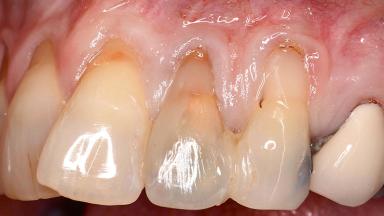

Early Implant Placement, Contour Augmentation, and Autologous Connective-Tissue Graft Using a Tunneling Technique to Replace an Upper Incisor with Generalized Gingival Recession

Variations in soft-tissue volume, evidenced either by an overabundance (Evian and coworkers 1993; Levine and McGuire1997; Dolt and Robbins 1997) or by a deficiency of soft or hard tissue can complicate implant-supported rehabilitations in the esthetic zone (Lorenzana 2008; Lorenzana and coworkers 2009). The present case illustrates the replacement of a failing upper left lateral incisor complicated by generalized severe gingival recession in the esthetic zone.

| Soft Tissue Anatomy | Intact | Defective | |

| Soft Tissue Contour and Volume | Significantly deficient |